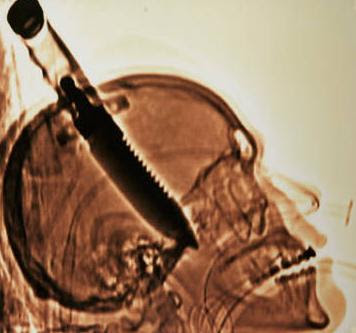

3. Terhunus dalam tengkorak

Michael Hill dari Jacksonville Florida ditikam di kepalanya dengan 7-inci pisau oleh orang tak dikenal yang muncul di depan pintu, 2007 lalu. Dia saat ini memegang Guinness World Records, Judul: "Objek Terbesar yang dikeluarkan dari tengkorak manusia."